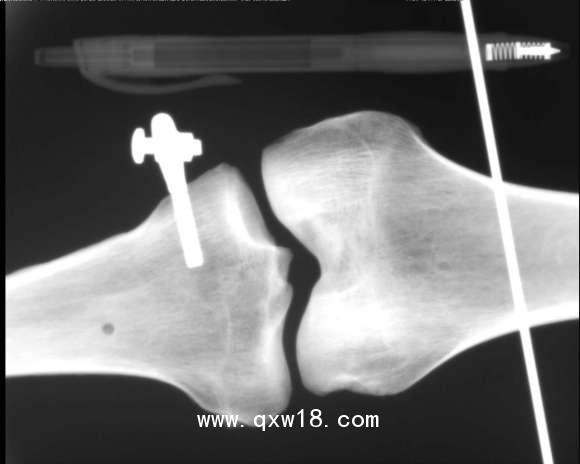

動物x光機

動物、海洋生物檢測儀,采用R160數(shù)字成像系統(tǒng)成像,?0.3微焦點射線管集約束散射線,數(shù)字成像,圖像清晰.儀器全數(shù)字化軟件操作功能;正反選圖像、圖像放大縮小、左右旋轉,前后旋轉、翻轉、數(shù)字化高清灰度專業(yè)圖像采集、千兆網(wǎng)端有線和無線連接,電腦即時成像、存儲和即時打印檢測效果圖片。

XDX-DF160B型?動物、海洋生物檢測儀;主要針對動物,海洋生物、魚類檢測;同時還可用于:玩具、蟲草、斷針、金屬異物等檢測